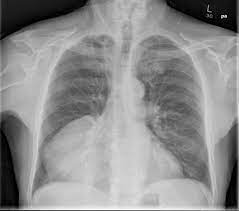

O diagnóstico das doenças do mediastino é realizado através de exames de imagem, como radiografia de tórax, tomografia computadorizada e ressonância magnética. Em alguns casos, pode ser necessária a realização de biópsias para obter amostras do tecido afetado e confirmar o diagnóstico.